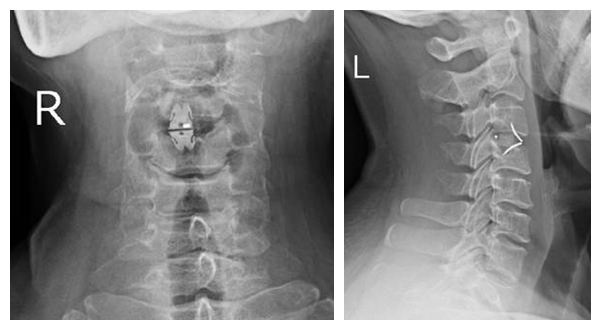

术后DR

刘女士及家属商量后决定行手术予转脊椎关节科。在脊椎关节科行颈椎前路颈3/4椎间盘摘除、椎管减压、椎间植骨融合内固定术。术后予预防感染、脱水消肿、营养神经、抗炎等对症支持治疗。现患者术后3周颈部及左上肢疼痛症状完全消失,双上肢无不适,可安静入睡,四肢肌力、肌张力正常。